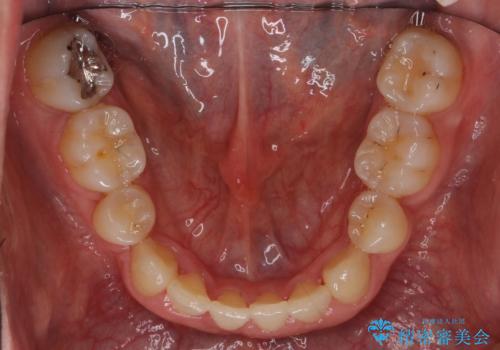

受け口 絶対に顎の手術はしたくない

- 受け口を主訴に来院。

かみしめもあり、骨も固く、歯根も長いためなかなか歯が動かず、患者様も治療する側も忍耐を要する長期戦となりました。